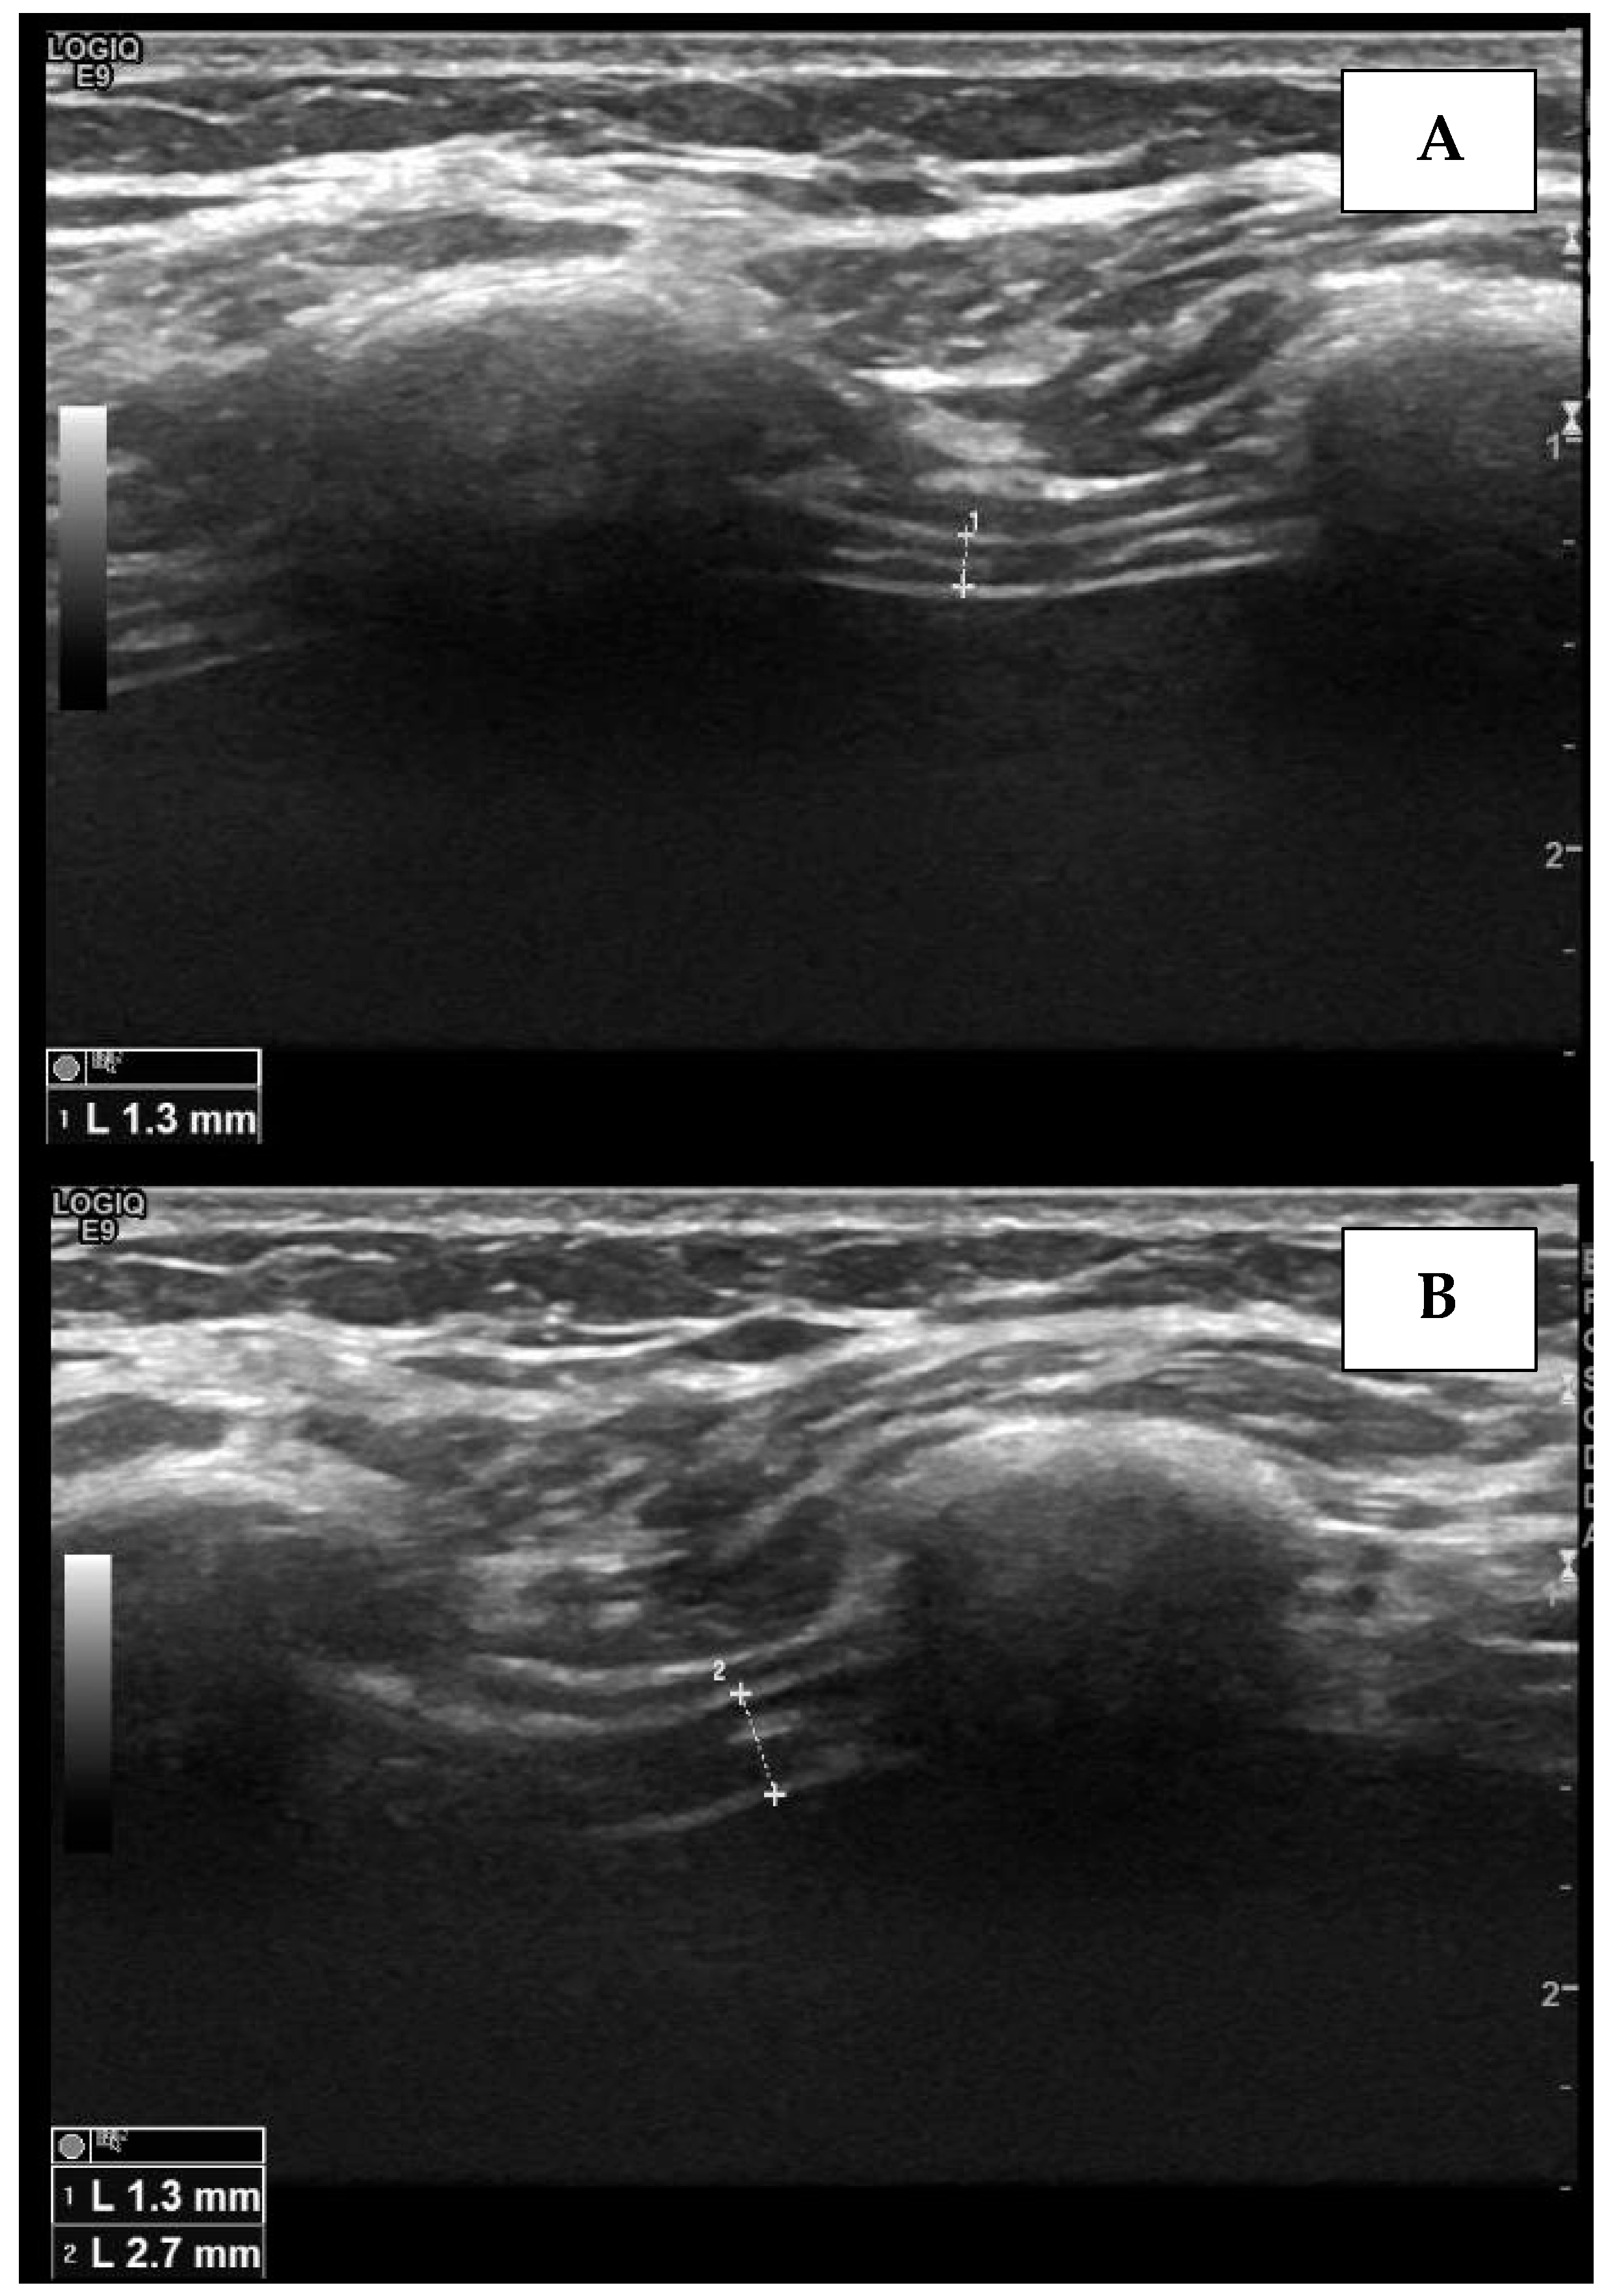

4.2. The Apposition Zone Approach

- Carrillo-Esper, R.; Pérez-Calatayud, Á.A.; Arch-Tirado, E.; Díaz-Carrillo, M.A.; Garrido-Aguirre, E.; Tapia-Velazco, R.; Peña-Pérez, C.A.; Espinoza-de Los Monteros, I.; Meza-Márquez, J.M.; Flores-Rivera, O.I.; et al. Standardization of sonographic diaphragmthickness evaluations in healthy volunteers. Respir. Care 2016, 61, 920–924. [Google Scholar] [CrossRef]

- Goligher, E.C.; Laghi, F.; Detsky, M.E.; Farias, P.; Murray, A.; Brace, D.; Brochard, L.J.; Bolz, S.S.; Rubenfeld, G.D.; Kavanagh, B.P.; et al. Measuring diaphragm thickness with ultrasound in mechanically ventilated patients: Feasibility, reproducibility and validity. Intensive Care Med. 2015, 41, 642–649. [Google Scholar] [CrossRef]